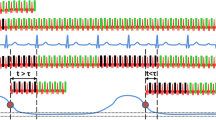

Figure 1a provides Bloch equation simulations of 0.55 T SNR and blood-myocardium CNR, scaled to simulated 1.5 T SNR and CNR with our clinical cine protocol. These simulations predicted that 0.55 T CNR would be most similar to 1.5 T with flip angle = 68°. Figure 1b provides representative images in a healthy subject for a range of parameters (flip angle, receiver bandwidth, TR and TE). For our 0.55 T breath-held cine imaging, we selected a receiver bandwidth of 350 Hz/Px, and a flip angle of 78°, which we preferred over the simulated optimum of 68°.

bSSFP parameter optimization for 0.55 T. (a) Simulations and (b) healthy subject imaging demonstrating parameter optimization for bSSFP cine imaging at 0.55 T by varying flip angle and receiver bandwidth (rBW). Simulated SNR and CNR are scaled relative to simulated 1.5 T SNR and CNR for our standard cine protocol. The yellow dots in (a) and yellow frame in (b) demonstrate the selected parameter combination

Additional file 1 provides a side-by-side comparison of image quality for matched parameters at both field strengths. At 0.55 T, SNR and CNR more closely match 1.5 T using the optimized protocol with higher flip angle and reduced receiver bandwidth. Notably, by using the 0.55 T protocol for imaging at 1.5 T, artifacts were introduced by the long-TR optimized for 0.55 T, and a 78° was infeasible at 1.5 T due to SAR restrictions.

Bloch equation simulations of our breath-held bSSFP protocols at 1.5 T and 0.55 T predicted that myocardial SNR at 0.55 T would be 50% of 1.5 T, blood SNR at 0.55 T would be 53% of 1.5 T, and 0.55 T CNR would be 55% of 1.5 T. SNR and CNR were measured in four healthy volunteers imaged at both 0.55 T and 1.5 T. After scaling SNR for differences in voxel size between 0.55 T and 1.5 T protocols, relative SNR between the two field strengths was measured to be 43 ± 6% in myocardium, 58 ± 6% in blood, and relative CNR was 48 ± 7%. Difference between measured and simulated relative SNR and CNR is attributed to the SNR-penalty associated with the coil g-factor for GRAPPA reconstruction at 0.55 T. The blood-myocardium contrast index, which was calculated from the absolute signal intensity difference normalized to the myocardium, was higher at 0.55 T (2.4 ± 0.81 at 0.55 T vs 1.98 ± 0.34 at 1.5 T, p = 0.0004), due to the application of a higher flip angle at 0.55 T causing signal suppression in the myocardium. Blood-myocardium contrast was sufficient for endocardial segmentation in all cases.